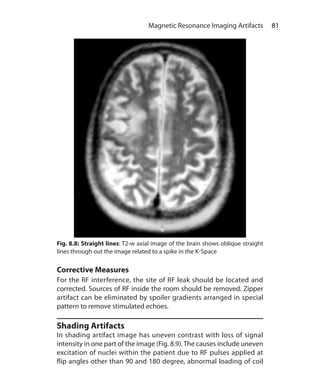

ShortTI IR sequences useTI in the range of 80-150 ms and example

is STIR. In Medium TI IR sequences, TI ranges from 300 to 1200 ms, and

example is MPRAGE (Siemens). Long TI ranges from 1500 to 2500 ms

and example is FLAIR.

SHORT TI (tau) IR Sequence (STIR)